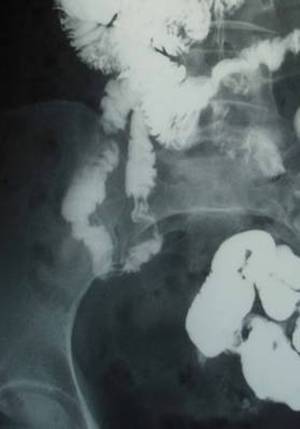

Centrul Medical Țuculanu a reușit de curând achiziționarea uneia dintre cele mai

de vârf tehnologii în domeniul imagisticii tubului digestiv,

sistemul de videoendoscopie digestivă cu capsulă.

Această explorare imagistică redefinește diagnosticul gastrointestinal oferind o

alternativă minim invazivă, neiradiantă și nedureroasă de vizualizare a

întregului tub digestiv în status natural.

Metoda s-a dovedit a fi sigură și eficientă, și foarte important, dintre

explorările digestive, cea mai agreabilă, tolerată și acceptată pentru pacient.

tehnologice a platformei de diagnostic și constă în ingestia unei camere video

de dimensiunea unei capsule de medicament, capabilă să filmeze cu înaltă

rezoluție imagini din tractul digestiv , imagini care sunt apoi transmise prin

intermediul senzorilor la un dispozitiv de stocare de imagini. La sfârșitul

procedurii toate imaginile sunt compilate cu ajutorul unui soft specializat în

procesare video și interpretarea aspectelor endoscopice.